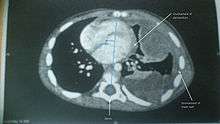

The most common site to which soft tissue sarcoma spreads is the lungs.